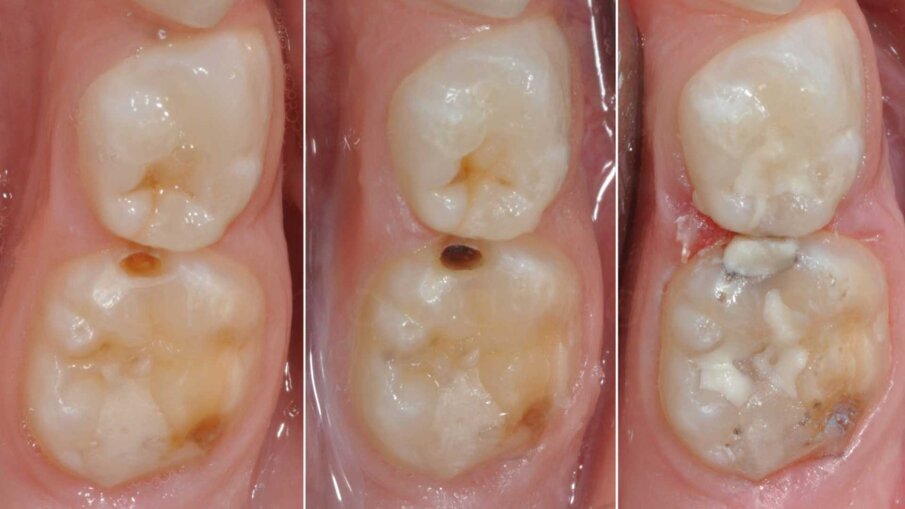

Costituisce il pilastro del minimo intervento e va applicato sempre e comunque mediante motivazione ad una corretta alimentazione e utilizzo ragionato di prodotti fluorati5 (dentifrici, gel, vernici). Ad oggi esiste una crescente evidenza di alta qualità riguardo la possibilità di poter trattare anche lesioni cariose avanzate attraverso terapie non invasive realizzate con prodotti a base di argento e fluoro ad alte concentrazioni (Riva Star Aqua, SDI)6 (Fig. 1).

Riservato a lesioni moderate e avanzate, consiste principalmente (ma non solo) nel trattamento restaurativo diretto eseguito in modalità atraumatica o convenzionale attraverso il principio della rimozione selettiva della lesione cariosa. Storicamente la fase di rimozione della dentina è da sempre stata intesa come non selettiva (o totale) ossia che si conclude solo allorquando si raggiunga la cosiddetta dentina “dura” (hard dentine) aumentando quindi il rischio di esposizioni iatrogene pulpari. In odontoiatria pediatrica sarà suggeribile quindi limitarsi a una rimozione selettiva (o parziale) ossia che si conclude nel momento in cui si raggiunga la cosiddetta dentina “affetta” (ma non infetta) di consistenza intermedia tra la dentina dura e la dentina rammollita (Leathery & Firm dentine). È evidente come questa distinzione intraoperatoria sia tutt’altro che semplice e oggettiva da eseguire; a questo proposito è crescente l’evidenza a supporto della rimozione chemio-meccanica della lesione cariosa, ovverosia sull’ausilio di un mezzo chimico (a base di ipoclorito o di enzimi derivati dalla papaina) in grado di facilitare l’operatore durante questa delicata procedura8 (Fig. 2).